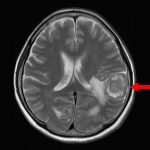

652

'25年7月

50代

右側頭葉神経膠腫

頭蓋内腫瘍摘出術

No.’25_54 手術前1

No.’25_54 手術前2